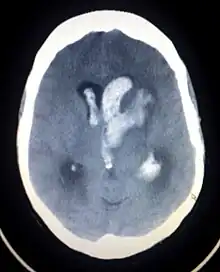

Altered level of consciousness

An intracranial hemorrhage, one cause of altered level of consciousness

An altered level of consciousness can result from a variety of factors, including alterations in the chemical environment of the brain (e.g. exposure to poisons or intoxicants), insufficient oxygen or blood flow in the brain, and excessive pressure within the skull. Prolonged unconsciousness is understood to be a sign of a medical emergency.[3] A deficit in the level of consciousness suggests that both of the cerebral hemispheres or the reticular activating system have been injured.[4] A decreased level of consciousness correlates to increased morbidity (sickness) and mortality (death).[5] Thus it is a valuable measure of a patient's medical and neurological status. In fact, some sources consider level of consciousness to be one of the vital signs.[3][6]

A lowered level of consciousness indicate a deficit in brain function.[4] Level of consciousness can be lowered when the brain receives insufficient oxygen (as occurs in hypoxia); insufficient blood (as occurs in shock, in children for example due to intussusception); or has an alteration in the brain's chemistry.[3] Conditions of the heart and conditions of the lungs can alter consciousness. Metabolic disorders such as diabetes mellitus and uremia can alter consciousness.[12] Hypo- or hypernatremia (decreased and elevated levels of sodium, respectively) as well as dehydration can also produce an altered LOC.[13] A pH outside of the range the brain can tolerate will also alter LOC.[9] Exposure to drugs (e.g. alcohol) or toxins may also lower LOC,[3] as may a core temperature that is too high or too low (hyperthermia or hypothermia). Increases in intracranial pressure (the pressure within the skull) can also cause altered LOC. It can result from traumatic brain injury such as concussion.[12] Ischemic stroke and brain bleeding are other causes of altered consciousness.[12] Infections of the central nervous system may also be associated with decreased LOC; for example, an altered LOC is the most common symptom of encephalitis.[14] Neoplasms within the intracranial cavity can also affect consciousness,[12] as can epilepsy and post-seizure states.[9] A decreased LOC can also result from a combination of factors.[12] A concussion, which is a mild traumatic brain injury (MTBI) may result in decreased LOC.